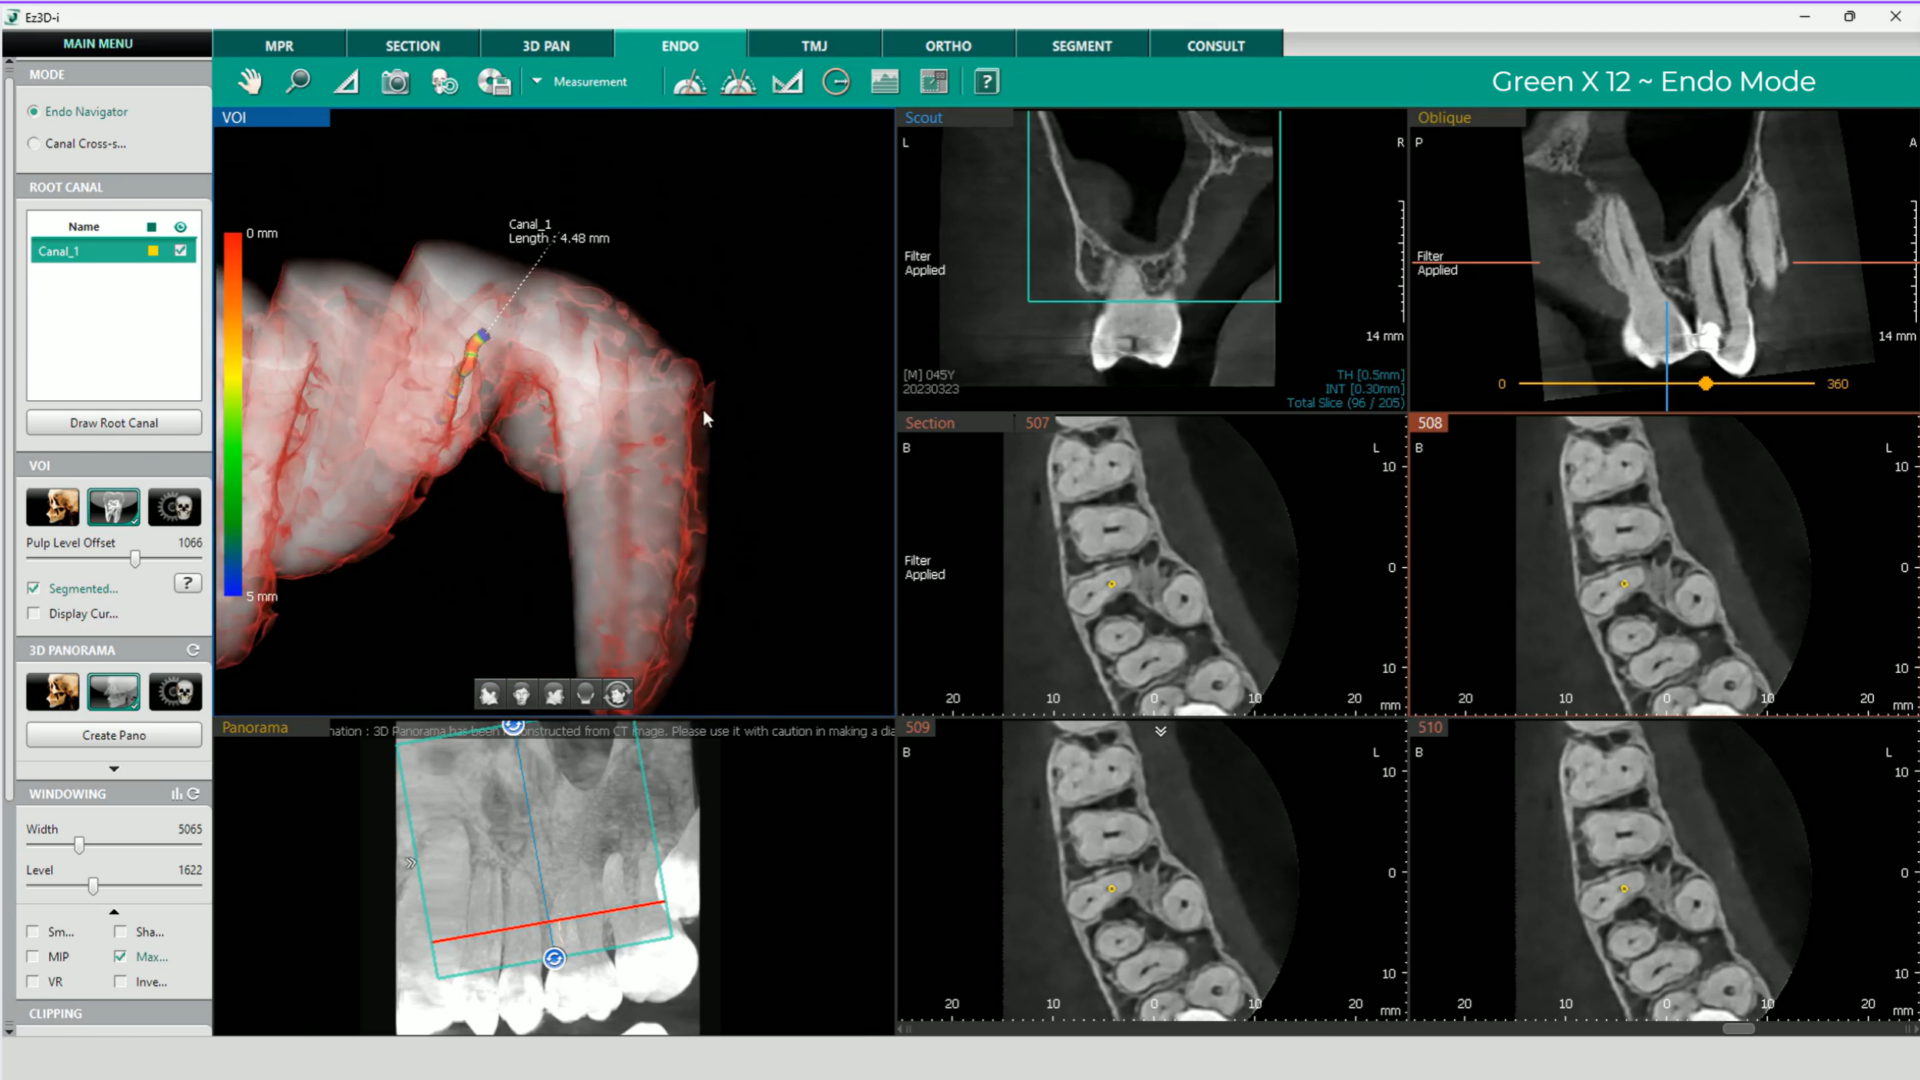

- Modul Endo cu cea mai înaltă rezoluție

Ideal pentru endodonție, modul Endo oferă imagini de volum de 4×4 cm cu dimensiunea voxelului de 49,5 microni. Această tehnologie permite diagnosticarea și tratamentul extrem de precis al regiunilor mici și detaliate.

Green X 12 este un sistem 4-în-1 avansat care combină imagistica Cone Beam CT (CBCT), panoramarea, scanarea modelelor 3D (CAD-CAM) și funcții endodontice specializate, oferind o soluție completă pentru diagnostic și tratament în stomatologie.

- SMART FOCUS: 1 scanare, 5 imagini

Cu o singură scanare, Green X 12 generează 5 imagini de înaltă rezoluție: trei imagini de 4×4 cm, o imagine de 12×8,5 cm și o imagine Auto PANO. Acest lucru reduce timpul de muncă pentru personal și minimizează expunerea la radiații pentru pacienți, asigurând un flux de lucru mai eficient și rapid.